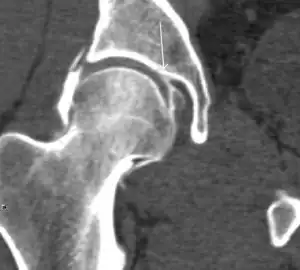

Computed Tomography

Due to radiation concerns, CT has been relegated after MRI in the study of intra-articular causes of hip pain. The only exception where CT is considered superior to MRI is in bone tumors, because of its ability in characterizing matrix calcifications, and in depicting the anatomy of acute traumatic fractures. Typical matrix calcifications include the following: (a) osteoid mineralization, like a dense cloud, (b) chondroid calcification, reproducing a punctate popcorn pattern, or (c) fibrous calcification, ground glass-like appearance. There are also tumors that typically do not show matrix calcification. CT is also used for accurate localization of the nidus in osteoid osteomas and this must be differentiated from Brodie’s abscess or a stress fracture. The current standard treatment of osteoid osteoma is percutaneous radiofrequency ablation and this is usually performed under CT guidance.[1]

Quite often, CT is widely available unlike MRI, especially in the acute setting. CT is performed in this setting when doubt about the existence of a fracture persists following plain radiograph. Modern multidetector computed tomography (MDCT) shows results comparable with MRI for detecting occult fractures.[1]

Due to the submillimeter resolution of MDCT arthrography, many authors consider this technique complementary to MR arthrography. It may even have superior sensitivity in detecting cartilage pathology, but lesser detecting labral tears.[1]

CT can also be used to obtain accurate measurement of the femoral version and torsion. The femoral version is measured by an angle formed between a line through the femoral head-neck axis and another horizontal line drawn between both ischial tuberosities. Normal values range between 5 and 25°. Retroversion is considered abnormal.[1]

Femoral torsion is the angle between a line along the femoral head and neck axis and a second line that is touching the posterior border of both femoral condyles. The normal value at birth is approximately 32° and decreases gradually with age. In adults, the normal value ranges from 10° to 20°.[1]